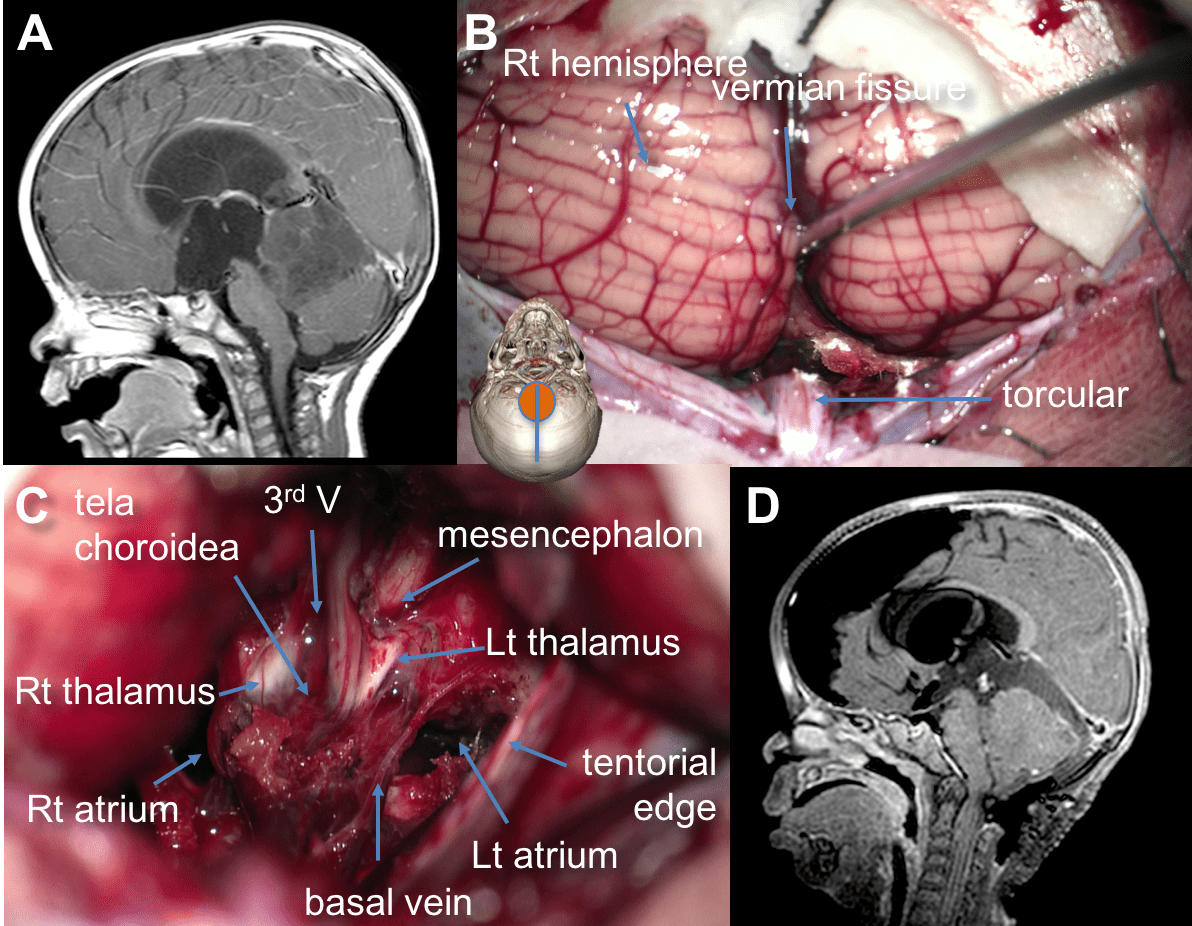

l’abord infra-tentoriel

il est plus adapté pour les tumeurs développées vers l’arrière (pointe du vermis) et les lésions de petite taille s’étendant dans le V3 au contact des veines cérébrales internes. il peut également être nécessaire lorsque l’espace entre la tente du cervelet et le corps calleux est très étroit, en particulier pour accéder à la cavité du 3ème ventricule ; cette voie donne alors un bon contrôle de la face inférieure de la toile choroïdienne et des veines cérébrales internes.

vue du dessous, la tente présente un aspect en entonnoir ; la dissection des limites latérales de la tumeur au niveau de l’incisure peut entraîner un saignement veineux.

il existe un risque de complications veineuses avec oedème post-opératoire.